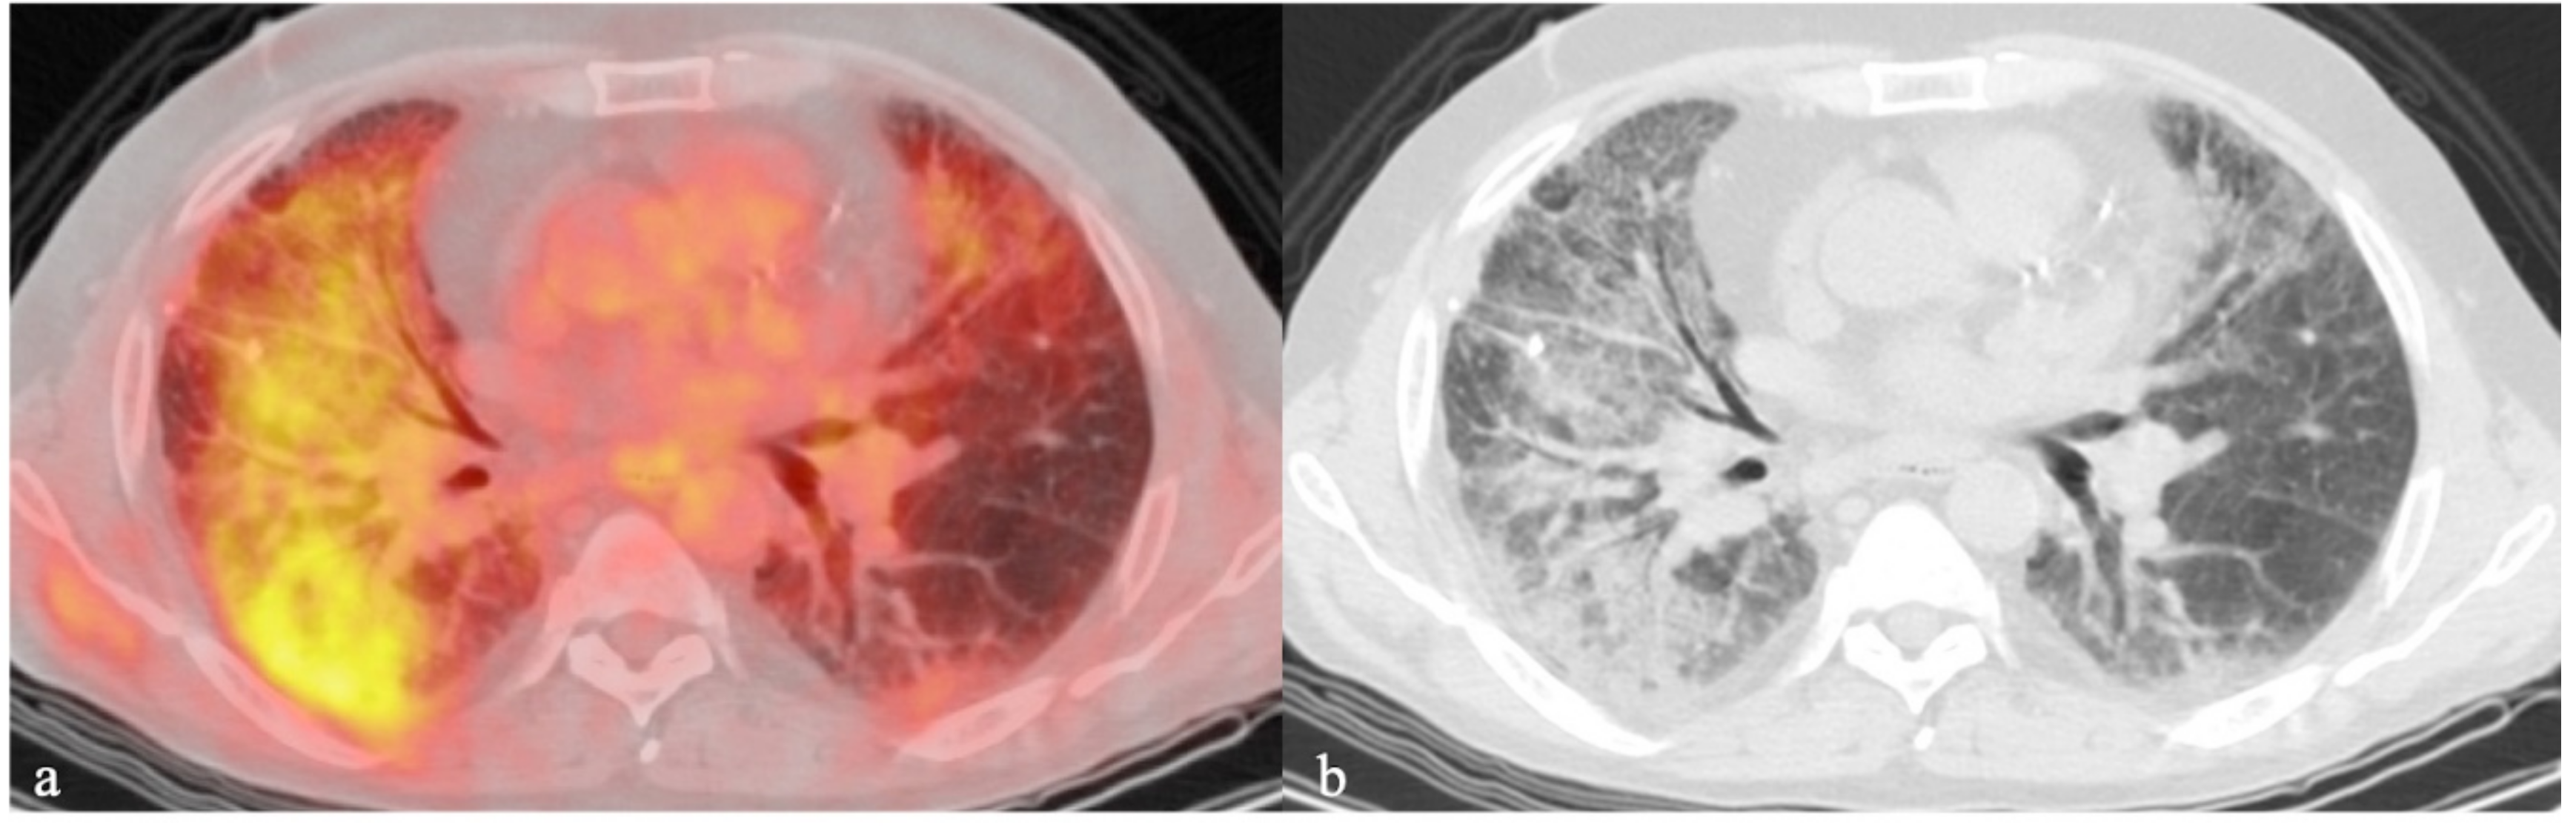

- Groves, A.M.; Win, T.; Screaton, N.J.; Berovic, M.; Endozo, R.; Booth, H.; Kayani, I.; Menezes, L.J.; Dickson, J.C.; Ell, P.J. Idiopathic pulmonary fibrosis and diffuse parenchymal lung disease: implications from initial experience with 18F-FDG PET/CT. J. Nucl. Med. 2009, 50, 538–545. [Google Scholar] [CrossRef]

- Verleden, S.E.; Gheysens, O.; Goffin, K.E.; Vanaudenaerde, B.M.; Verbeken, E.K.; Weynand, B.; Van Raemdonck, D.E.; Verleden, G.M.; Vos, R. Role of 18F-FDG PET/CT in restrictive allograft syndrome after lung transplantation. Transplantation 2019, 103, 823–831. [Google Scholar] [CrossRef]